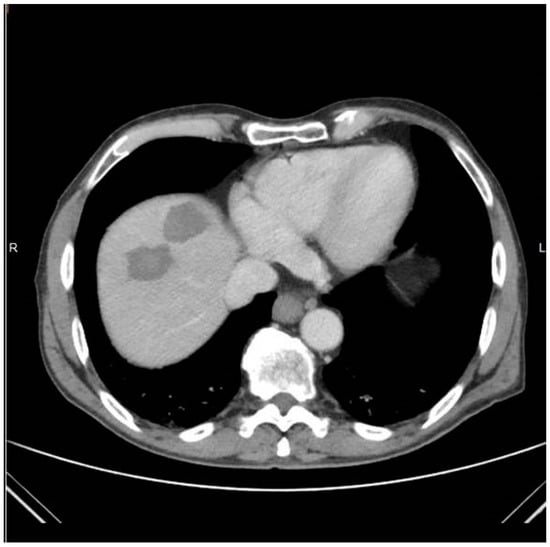

Demographic and clinical data of patients and lesions included in the present study are presented in Table 1. The sample consisted by 10 participants (16 lesions). The mean age of the included patients was 60.60 years (SD = 9.25 years). Neoplasmatic substrate included: hepatocellular carcinoma [2/10 (20%)], colorectal carcinoma [4/10 (40%)], gastrointestinal stromal tumor [2/10 (20%)], and myeloid carcinoma of the thyroid gland [2/10 (20%)]. The mean size of the lesions was 20.37 ± 7.29 mm, and maximum tumor size ranged from 8 to 30 mm Mean follow-up time was 3.4 months (SD = 1.41) months. Most of the participants were males, with the percentage being 80%. In the 2 HCC patients’ percutaneous ablation was decided in the multidisciplinary tumor board meeting as a first-line therapy due to co-morbidities, lesion location, and size (< 3cm in diameter). As far as the four patients with colorectal cancel liver metastases are concerned, ¾ patients involved metachronous lesions post surgery of the original intestinal tumor and systemic chemotherapy and ¼ patients suffered from synchronous hepatic lesions. In this last patient, percutaneous ablation was performed post systemic chemotherapy, whilst surgical operation of the intestinal tumor was performed the morning post ablation. In the remaining 4/10 patients, percutaneous ablation was performed in metachronous metastatic disease resistant to systemic therapies and post surgical operation of the original tumor. Technical success was 100% (i.e., antenna placement at the target lesion was successful in all patients). There was no need for hydrodissection or any other ancillary methods.

The mean total duration of the procedure from entrance to exit of the patient was 49.45 (SD = 7.53 min). Specifically, a median of 7 min was necessary for planning time and 12 min for insertion time. Whenever deemed necessary (4/16 sessions), the microwave antenna was re-positioned and a second ablation session was performed, so as to ensure that the final ablation completely encompassed both the target tumor and an annular safety zone around it that was a minimum of 5 mm thick. Navigation was used for all four repositioning. A median of 11 scans was performed including planning and control scans as well as a scan during ablation (Figure 3) and immediate imaging follow-up with 3 scans (prior to and post contrast medium injection in the arterial and portal venous phases).

Figure 3. Same patient as in Figure 1 and Figure 2: Computed tomography axial scan during evaluation of the placement of the antenna in the target lesion and potential gas bubbles dispersion.